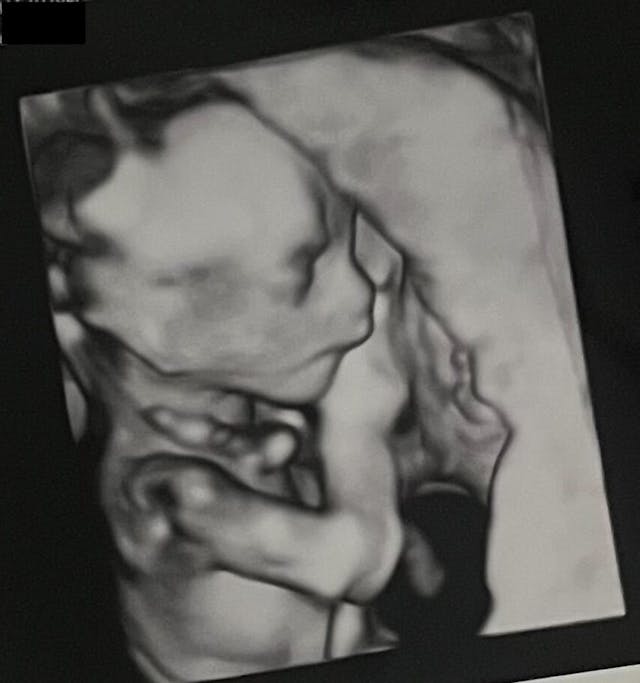

Fast forward to our ultrasound: we went in and saw our beautiful baby girl on the screen, moving around and sucking her thumb, and after a long analysis the doctors assured us that all looked to be well, but they couldn’t be 100% sure without an amniocentesis.